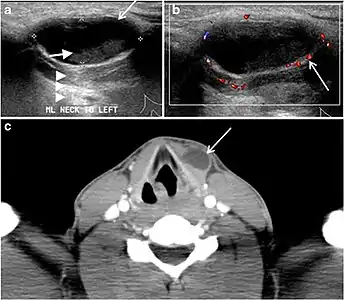

Fig. 7. A 51-year-old female patient post total thyroidectomy for PTC with elevated thyroglobulin measurement. an Axial non-enhanced CT scan of the neck at the level of the thyroid bed demonstrates a well-defined, rounded, homogenously dense soft tissue situated between the trachea and left internal jugular vein (white arrow). b Transverse ultrasound image of the neck demonstrates a well-defined, homogeneous, hypoechoic soft tissue nodule measuring 6 mm (white arrow) with no detected micro-calcifications. Biopsy showed a predominantly residual normal thyroid tissue with micro-foci of PTC.[1]

Fig. 8. A 48-year-old male patient post total thyroidectomy with PTC recurrence. a Transverse greyscale ultrasound of the neck demonstrates a left thyroid bed heterogeneous, predominantly hypoechoic irregular lesion with calcifications (white arrow). b A spot image of iodine 123 total body scan of the neck demonstrate a focus of abnormal radiotracer uptake at the left thyroid bed (Black arrows) between the annotated markers. c Enhanced axial CT scan of the neck demonstrates an enhancing large left thyroid bed mass (white arrow) with no calcifications. The lesion exerts a mass effect on the oesophagus (black arrow) and is inseparable from the trachea.[1]

Fig. 9. A 58-year-old male patient with persistence PTC at thyroid bed with hypervascular nodal metastasis. a–c Transverse greyscale and colour Doppler neck ultrasound demonstrate hypoehoic soft tissue in the left thyroid bed (white arrow in a). There are a heterogeneous enlarged lymph nodes at level 2 and 3 with markedly increased vascularity (white arrow in b and c). d–f Enhanced axial CT images of the neck demonstrate a 2.7 × 1.4 cm hypodense soft tissue lesion anterior to the left carotid sheath (white arrow). There are left-sided enhancing abnormal and enlarged lymph nodes at cervical level 2 and 3 (black arrows).[1]